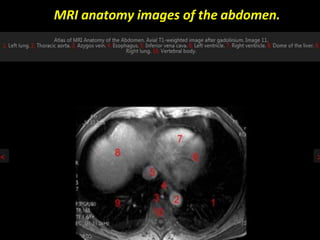

MRI anatomy images of the abdomen.

MRI anatomy imagesof the abdomen.